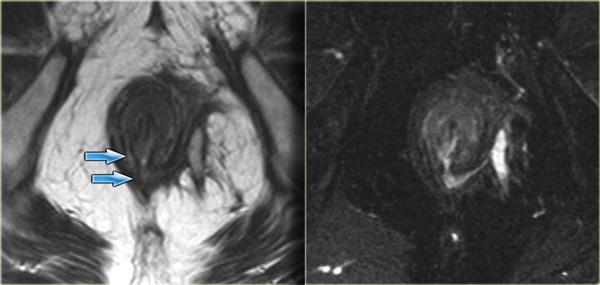

Bệnh nhân này đã được chẩn đoán trước đó là rò liên cơ thắt, với tổn thương niêm mạc ở vị trí 1 giờ.

Trong lòng đường rò có một cấu trúc dạng tuyến tính với tín hiệu thấp.

Đây là chỉ Seton đã được đặt vào để điều trị đường rò.